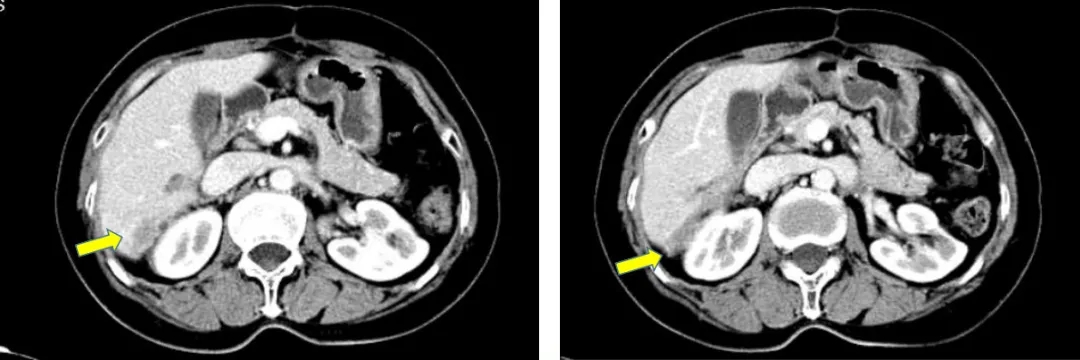

2021.4.23复查CA125上升至70.2U/ml。2021.4.24 CT:肝肾隐窝病灶增大,考虑复发。患者退出BGB-290临床试验。

2021.5.8 PET-CT:肝肾隐窝转移灶。2021.5.12复查CA125水平为95.5U/ml。